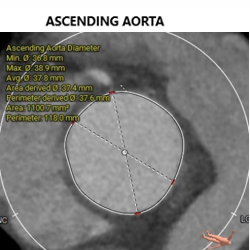

• 升主动脉 直径37.6(40mm高度)